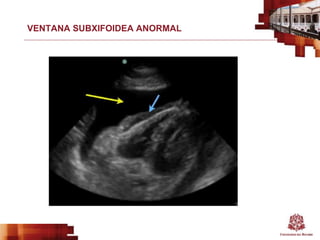

VENTANA SUBXIFOIDEA NORMAL

VENTANA SUBXIFOIDEA ANORMAL